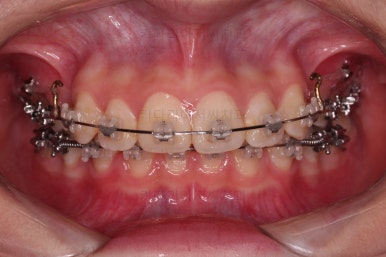

초진 시 입안의 모습입니다.

위아랫니가 많이 삐뚤진 않는데 뭔가 이상하죠?

어금니 맞물림은 지그재그로 잘 맞물려 있는데 위아래 앞니는 서로 앞뒤로 매우 멀죠.

비밀은 매우 자연스러워 보이지만 아래 앞니 2개가 선천 결손인 상태였습니다.

앞니끼리 맞물리지 않다보니 아래 앞니는 점점 솟구쳐 과개교합(깊게 맞물려 아래 앞니가 거의 보이지 않는 현상)이 되게 됩니다.